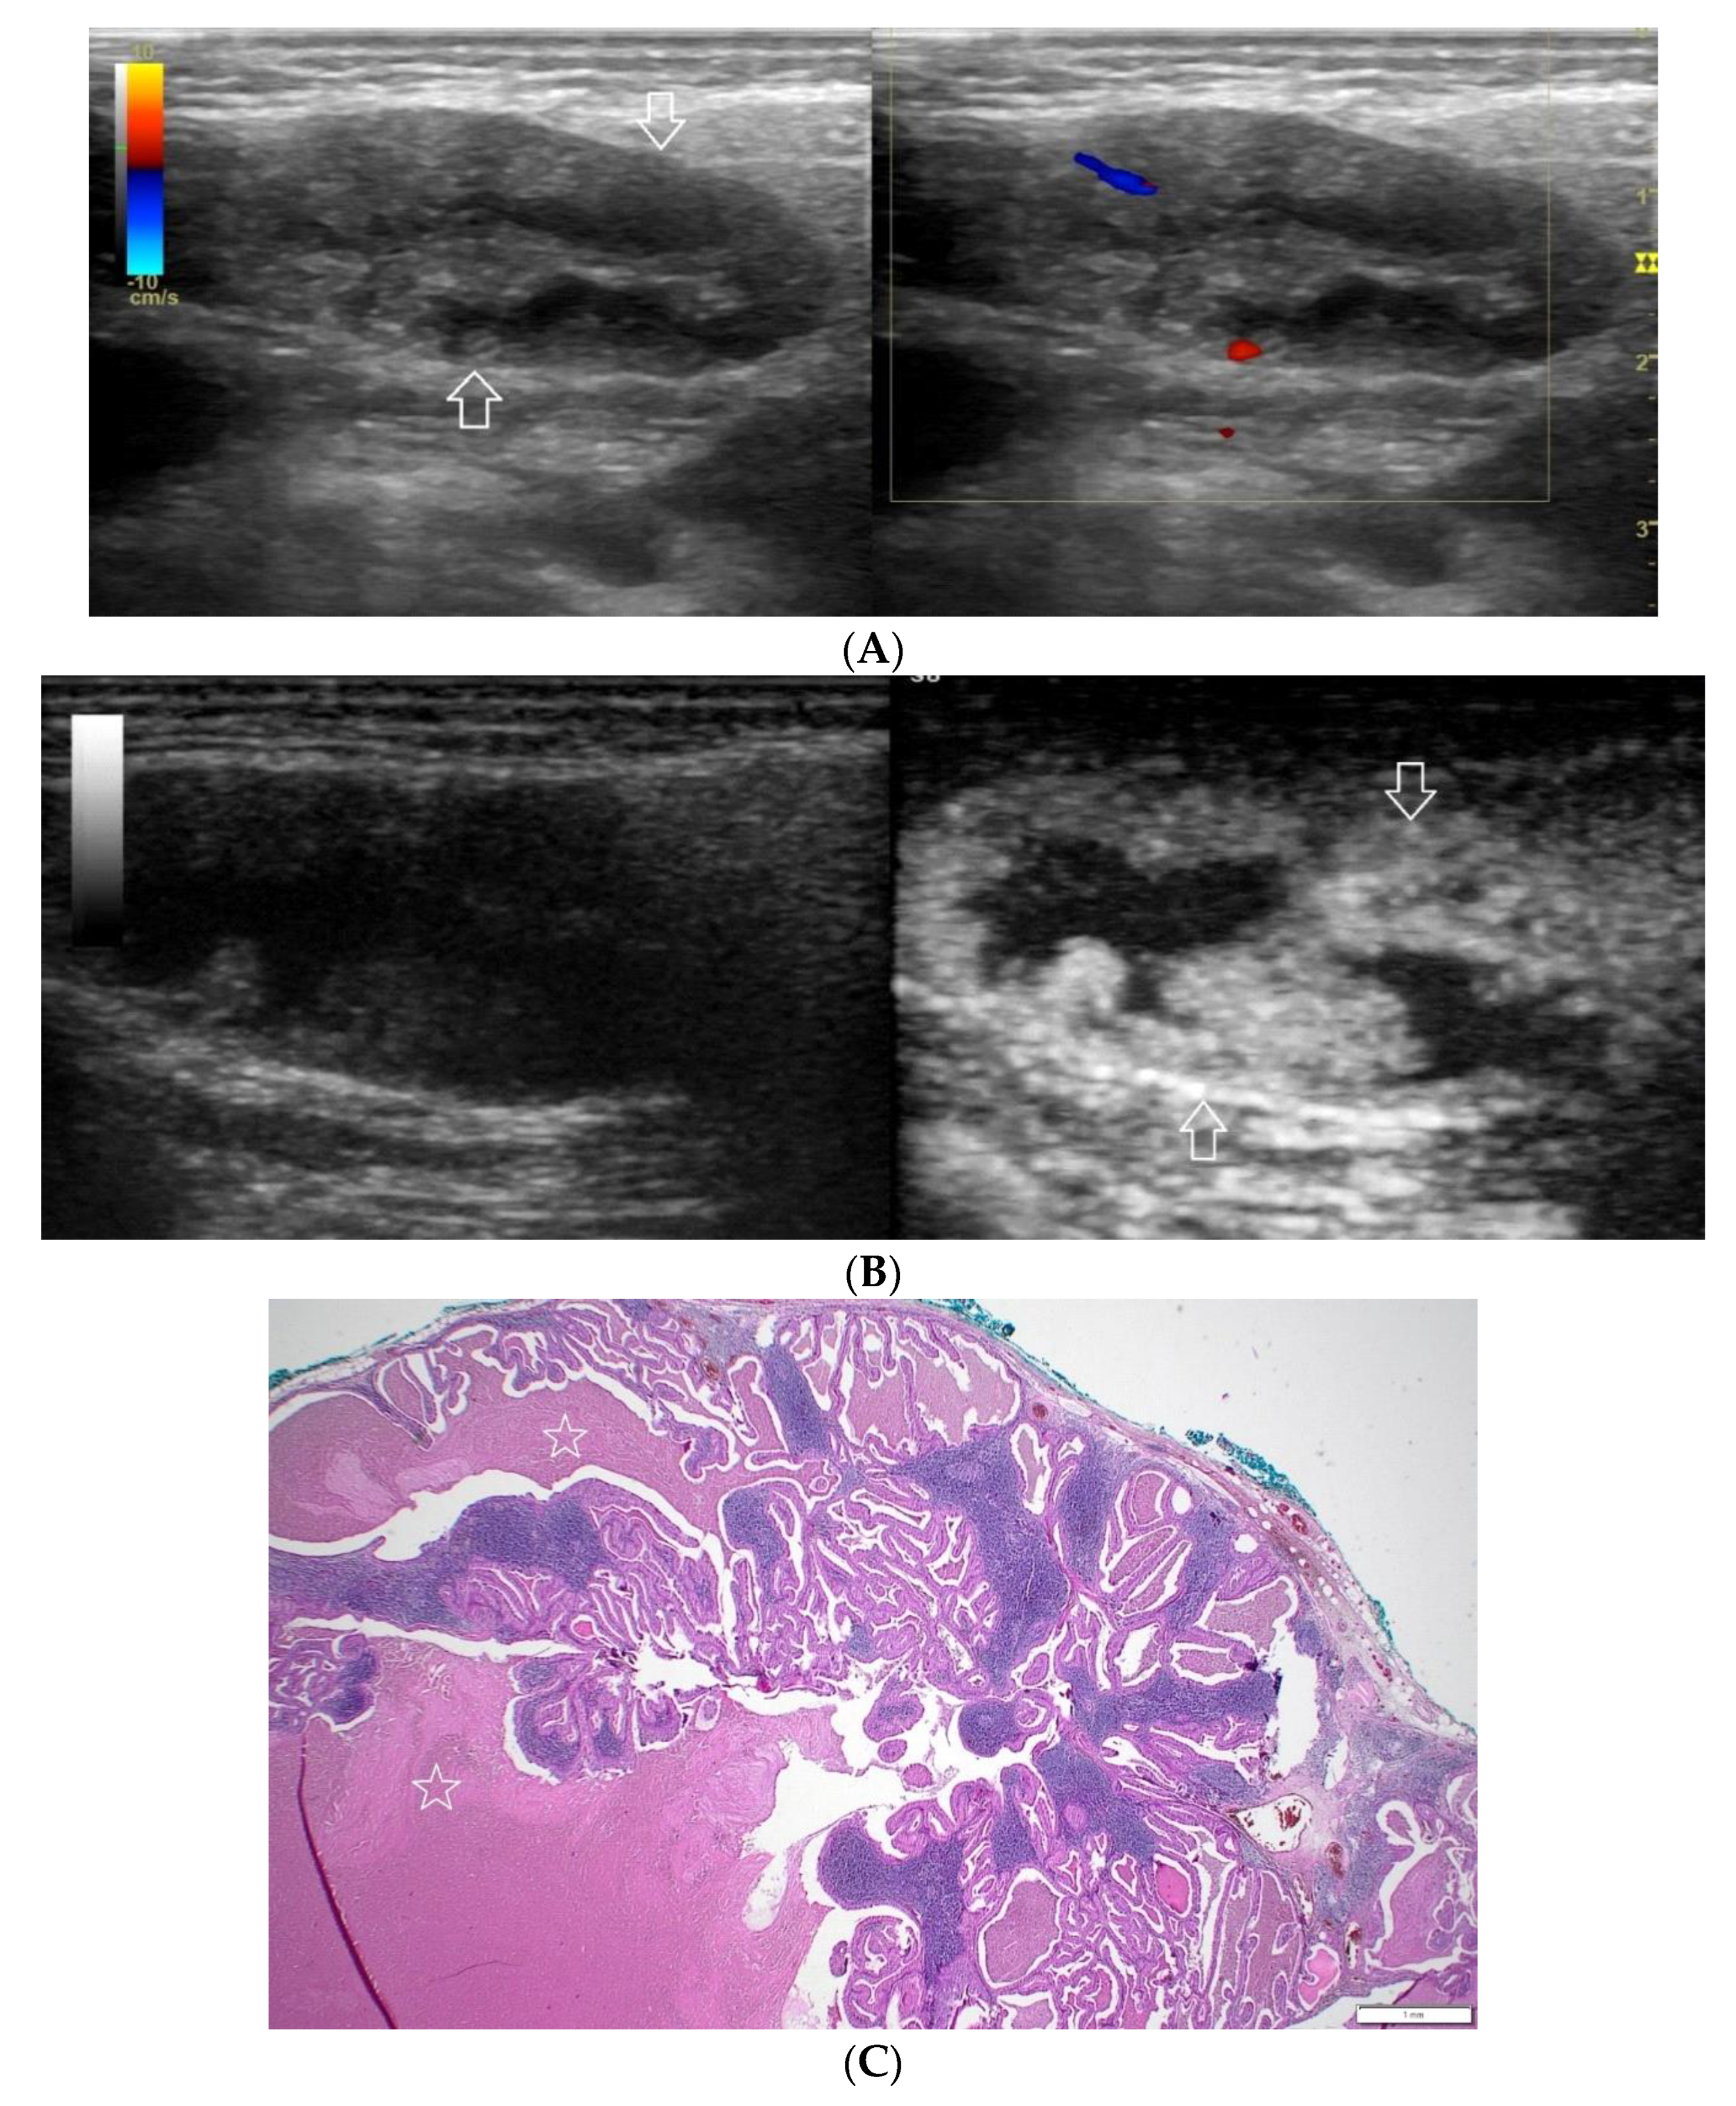

Figure 6.

(A−C) Lymphoepithelial cyst. (A) Routine ultrasonographic examination in B presentation and colour Doppler: an oval hypoechogenic well-demarcated focal lesion of a homogeneous echostructure (white arrows). On CD, no blood flow within the lesion is observed. (B) Contrast-enhanced imaging in arterial phase: no contrast enhancement of the lesion is observed (white arrows). (C) Pathomorphological image, H & E stain. A large area containing fluid with no signs of neoplastic growth.